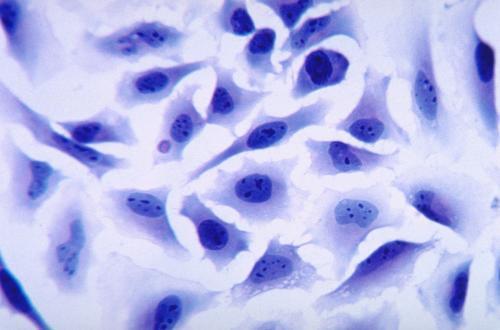

病毒載體:最常用的基因遞送載體之一1.1 病毒載體是通過改造病毒來遞送基因的常用工具病毒載體是一種常用的分子生物學(xué)工具,可將遺傳物質(zhì)帶入細(xì)胞,原理是利用病毒具有傳送其基因組進(jìn)入其他細(xì)胞進(jìn)行感染的分子機制。病毒是一種由核酸分子和蛋白質(zhì)構(gòu)成的非細(xì)胞形態(tài)生物,能夠攜帶基因進(jìn)入受體細(xì)胞,經(jīng)開發(fā)和改造后可用作CGT載體。由于病毒的多樣性及宿主機體的高度復(fù)雜性,目前

來源:藥渡撰文:四月的雨 編輯:丸子1概述許多藥物在體內(nèi)往往具有溶解度低、保留時間短、生物利用度低以及靶向能力較差等限制,而且大分子藥物如核酸和蛋白質(zhì),還很容易被各種酶快速降解,從而失去活性。基于細(xì)胞的給藥策略因其獨特的生物學(xué)特性,如優(yōu)良的生物相容性、低免疫原性、較長的循環(huán)時間以及跨越生物屏障的能力而備受關(guān)注。多種細(xì)胞可作為功能載體而用于藥物的遞送,如紅細(xì)胞、干細(xì)胞以及淋巴細(xì)胞等。由于這些細(xì)